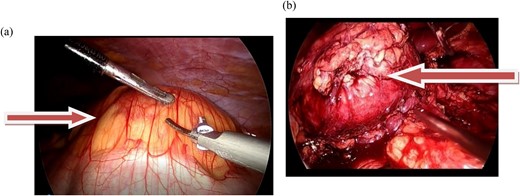

Laparoscopic transperitoneal tumorectomy was performed. During the transperitoneal approach, the tumor was observed anterior to the left kidney (Fig. 2a and b).

(a and b) The images show the laparoscopic view of a left retroperitoneal mass.